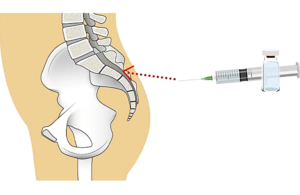

仙骨裂孔硬膜外神経ブロック

腰臀部の痛みや下肢の神経痛が強いときに行う神経ブロック治療です。

主に腰部椎間板ヘルニア・腰部脊柱管狭窄症に対して行います。罹患神経周囲に薬剤が届き神経の炎症や痛みの悪循環をブロックします。数回やっても効果の少ないときは中止します。ブロック後20~30分休んで頂きます。

| 初回 | 3割負担 約3,000円 |

| 2回目以降 | 約1,100円 |

超音波ガイド下で刺入